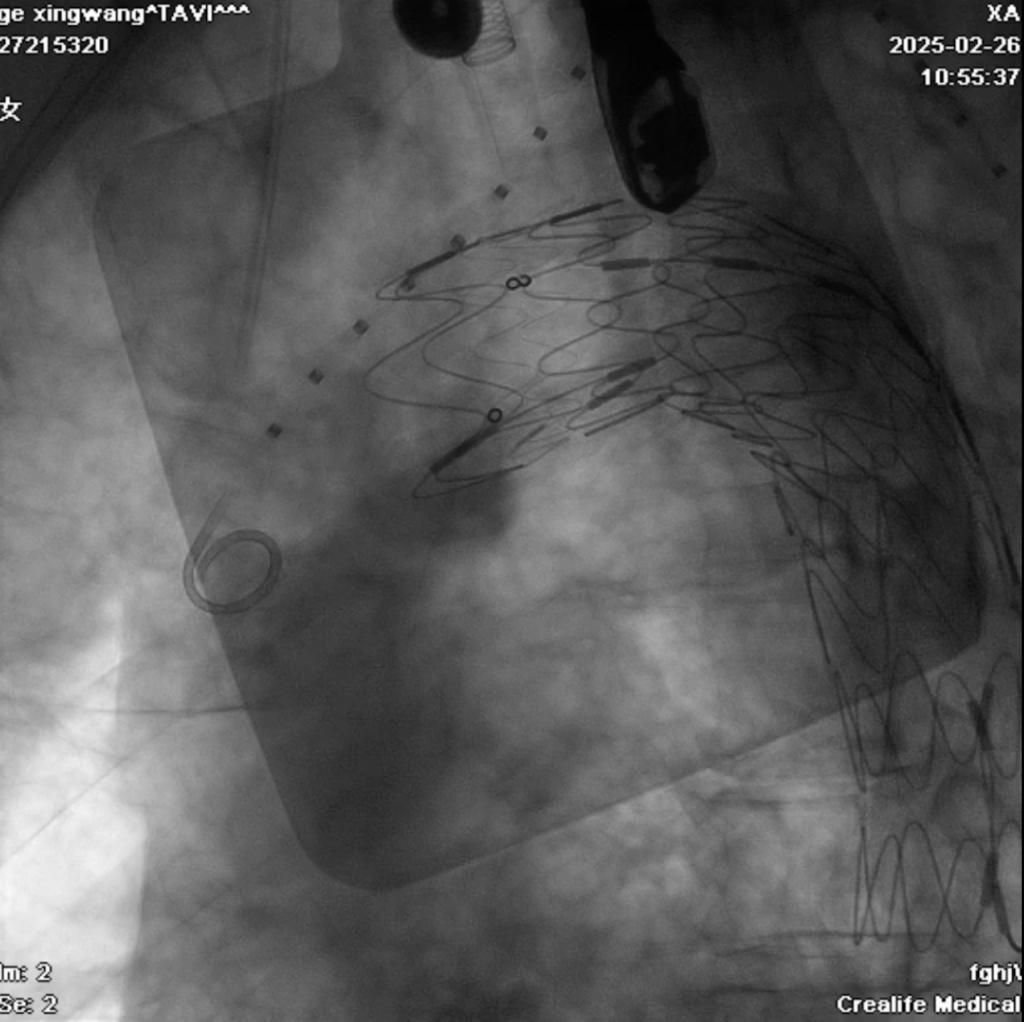

患者为77岁男性,因“反复出现活动后胸闷气喘3月”入院。患者入院后相关检查提示病情较为复杂:先天性主动脉瓣二瓣化伴重度主动脉瓣狭窄+主动脉穿透性溃疡+重度肺部疾病,考虑到外科手术风险极高,经心血管内科3病区梁有峰主任团队和相关科室充分讨论,决定采用一站式TAVR+TEVAR手术方案。手术由心血管内科联合心脏外科、麻醉科、心脏超声科,重症医学科等多学科团队共同完成。手术团队首先在主动脉溃疡破口处精准释放覆膜支架,随后经股动脉入路,成功完成经导管主动脉瓣置换术,应用介入微创技术一次性解决了主动脉瓣重度狭窄及主动脉穿透性溃疡等问题,整个手术过程顺利,术后第二天由ICU病房转入普通病房,目前患者已康复出院。